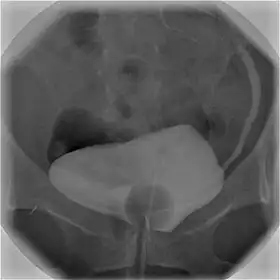

Cystography image showing contrast in the urinary bladder and left ureter (right side of image).

Cystourethrography is a radiographic, fluoroscopic medical procedure that is used to visualize and evaluate the bladder and the urethra.[1] Voiding and positive pressure cystourethrograms help to assess lower urinary tract trauma, reflux, suspected fistulas, and to diagnose urinary retention. Magnetic imaging (MRI) has been replacing this diagnostic tool due to its increased sensitivity.[2] This imaging technique is used to diagnose hydronephrosis, voiding anomalies, and urinary tract infections in children. abnormalities.[3]